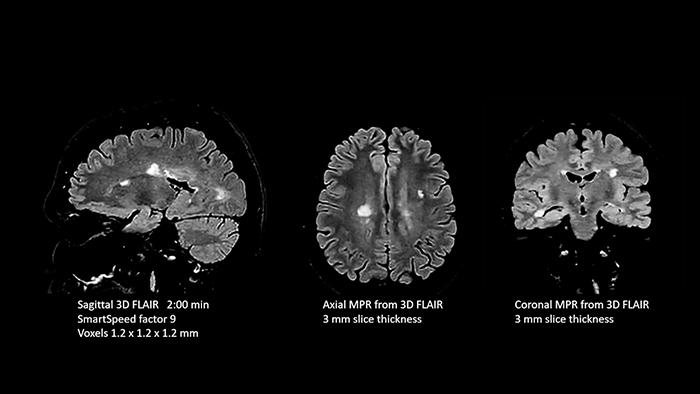

- White matter lesions in brain

In this examination SmartSpeed is used to reduce scan times. All three FLAIR orientations were obtained with only one 3D sequence using SmartSpeed. Performed with 1.5T Ambition X, dS Head coil.

- White matter lesions in brain

In this examination SmartSpeed is used to reduce scan times. All three FLAIR orientations were obtained with only one 3D sequence using SmartSpeed. Performed with 1.5T Ambition X, dS Head coil.